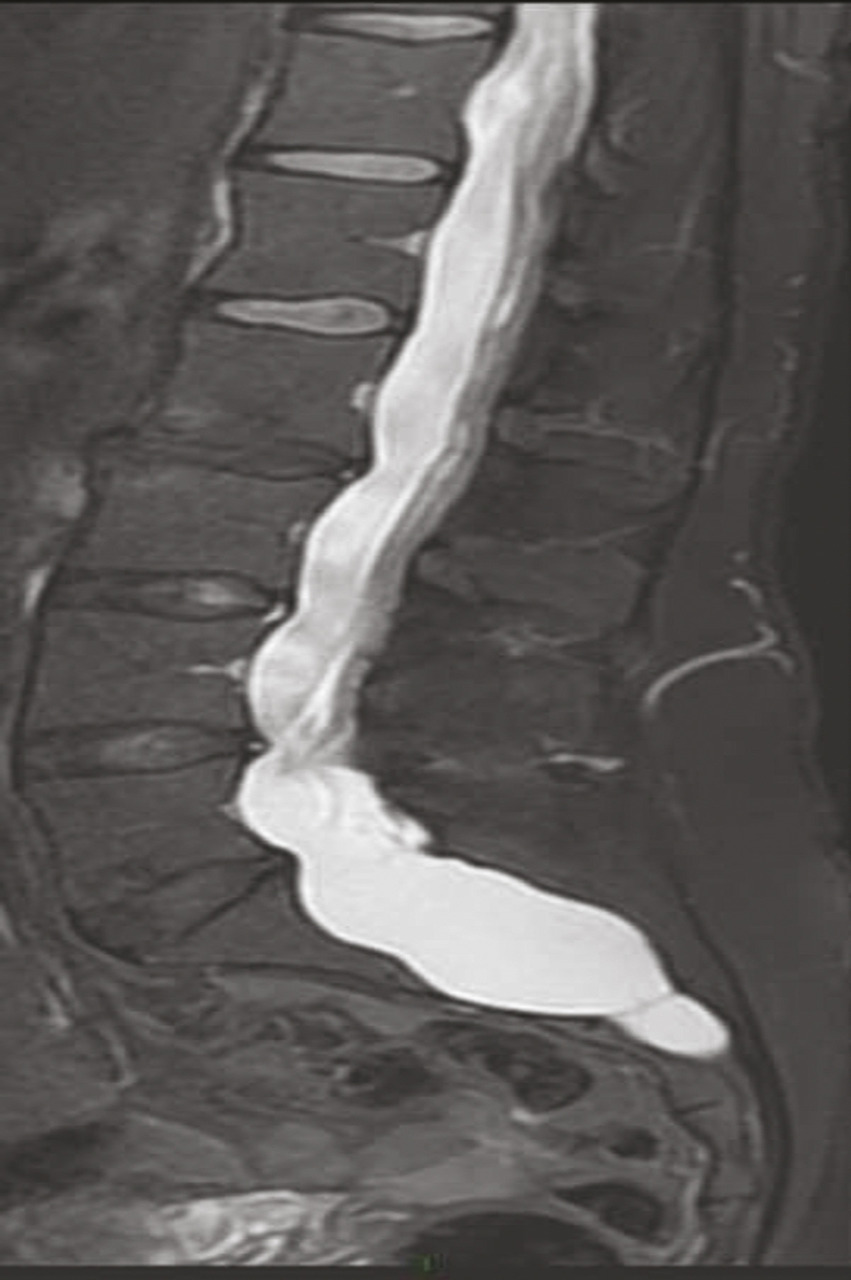

Les vertèbres peuvent être déformées par une ectasie du sac dural (fig. 3 ), visible essentiellement à la tomodensitométrie ou à l’imagerie par résonance magnétique (IRM). Les symptômes associés à cette ectasie durale restent mal connus. Elle peut être associée à des céphalées en rapport avec une hypotension du liquide céphalorachidien dont la symptomatologie est proche du syndrome post-ponction lombaire.

Les vertèbres peuvent être déformées par une ectasie du sac dural (